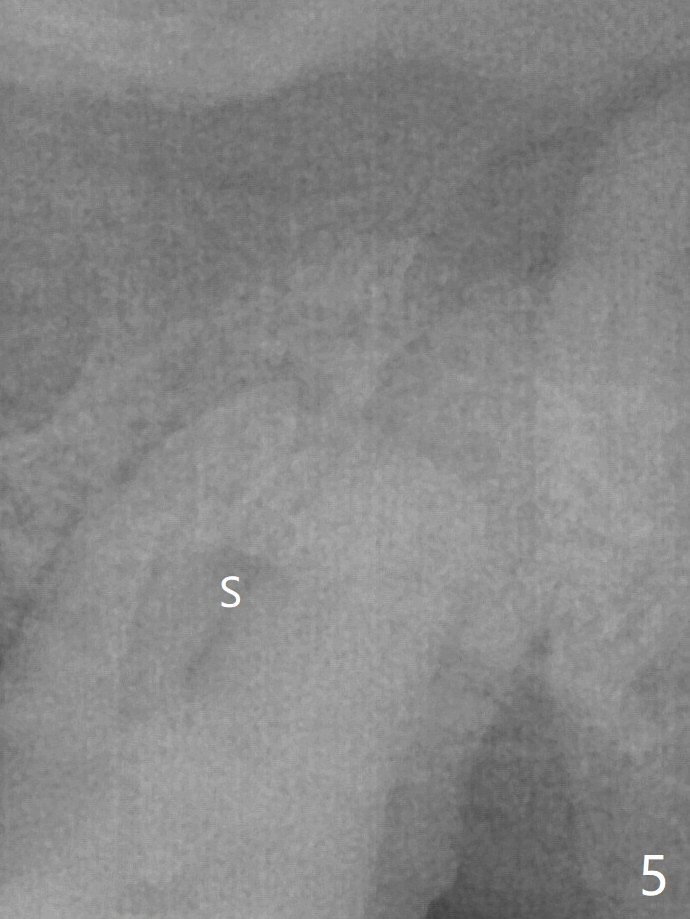

86岁男左上7折裂(图一),要求拔除,经过讨论(7拔除后,4-6悬臂桥可能断裂,对植体产生创伤,图二(左下7存在)),同意植骨。拔牙时发现中隔特别粗大(图三,五:S),三个牙槽窝根尖好像在中隔下面相互交通,擤鼻涕却没有气泡,仿佛与上颌窦没有相通。艰难清创后,放置Vanilla骨粉(图三),腭侧根特别容易填满,而颊侧根填入许多骨粉,术后CT远中颊侧骨粉尤其多(图四),上颌窦粘膜增厚(原来有季节性过敏)。术前根尖片显示远中颊侧根尖周围阴影很长(图五,六(虚线))。第二天早上鼻出血(仅有一次),今后牙槽窝明显比牙根长,清创控制深度,先放置胶原塞或PRF膜,后放骨粉。病人已经购买水牙线。术后7天树脂敷料稳定,局部卫生好(图七),骨粉好像进入上颌窦后部(图八)。术后1.5个月树脂敷料仍在原位,很容易撤除,牙槽窝愈合(图九),骨粉好像没有丢失(图十)。